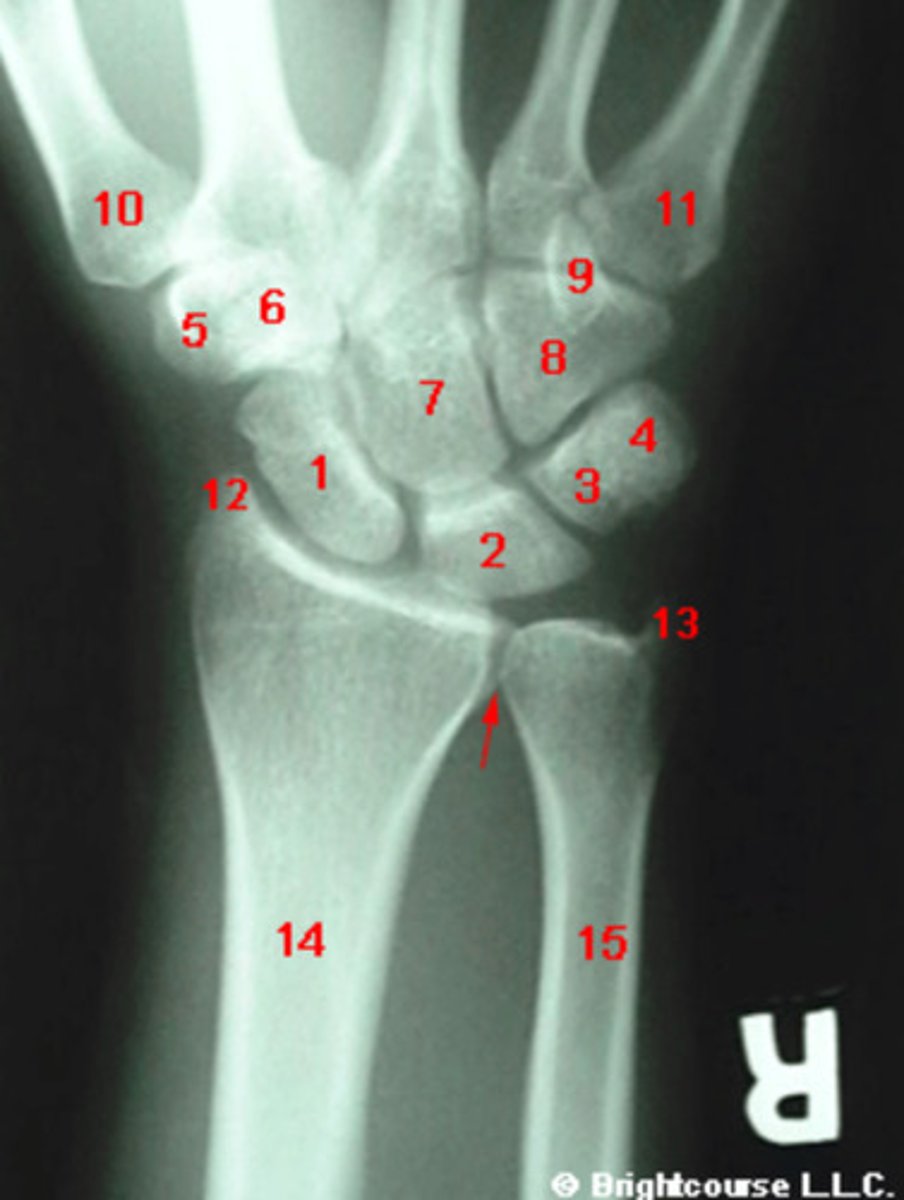

PA, internal oblique, and lateral

What are the standard plain film radiographic projections for the wrist?

What is the normal range for the Carpal angle?

What is the normal range for the radioulnar angle?

What is the normal range for the radius angle?

What conditions can alter the normal carpal alignment?

Capitate

What structure is indicated by number 7?

Scaphoid

What structure is indicated by number 1?

What structure is indicated by number 2?

What structure is indicated by number 3?

What structure is indicated by number 5?

What structure is indicated by number 6?

What structure is indicated by number 8?

What structure is indicated by number 13?

Carpal angle

What angle is being assessed in this image?

3 arcs of carpal alignment

What is being assessed in this image?

Radius angle

Radioulnar angle